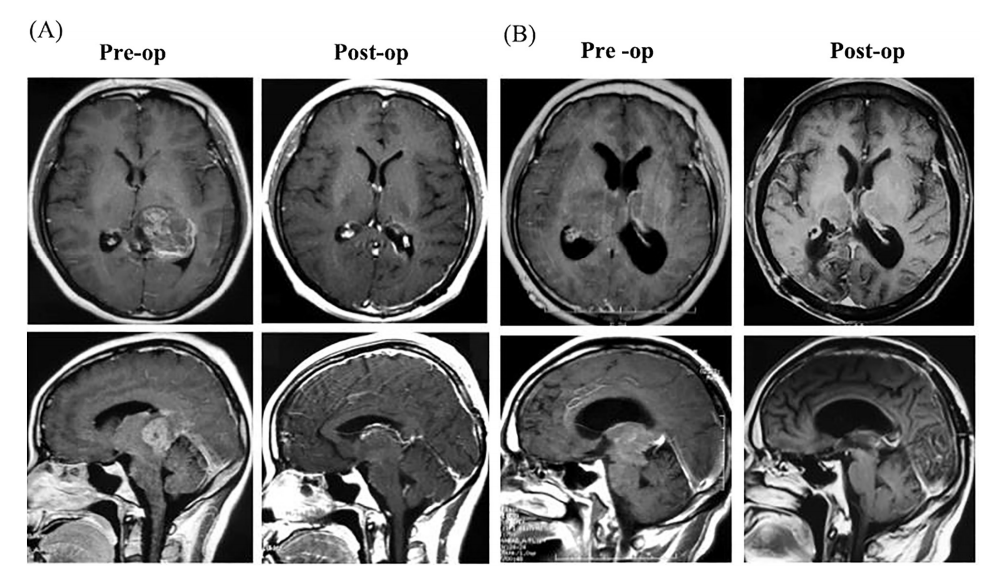

丘脑胶质瘤2例。A、术前MRI轴位和冠状位增强切片显示左侧高级别胶质瘤,肿瘤经顶侧脑室入路切除。B.术前MRI轴位和冠状位增强右侧高级别胶质瘤,经顶侧脑室入路切除肿瘤